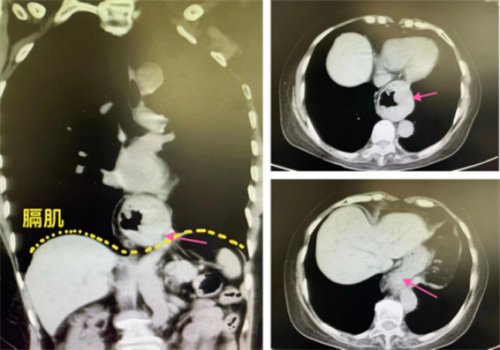

“已经出现了比‘胃食管反流’更严重的吞咽困难、腹痛反酸、呕吐等症状,对症药物治疗效果又不理想,高度怀疑‘食管裂孔疝’!”荆门市人民医院胃肠外科·疝与腹壁外科范金强表示,CT影像能清晰看到王奶奶本该在腹腔的胃(部分组织)跑到了胸腔内,结合病史确诊为“食管裂孔疝”。

▲ct影像显示部分胃组织“跑”到了胸腔